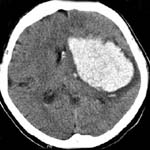

<°íÇ÷¾Ð¼º

³úÃâÇ÷>

<¼ö¼ú

Àü> <¼ö¼ú

ÈÄ>

¿ìÃø

Çǰ¢ºÎ ÃâÇ÷ȯÀÚÀÇ ³úCT¼Ò°ß(¼ö¼úÈÄ Ç÷Á¾ÀÌ

Á¦°ÅµÇ¾îÀÖ´Ù)